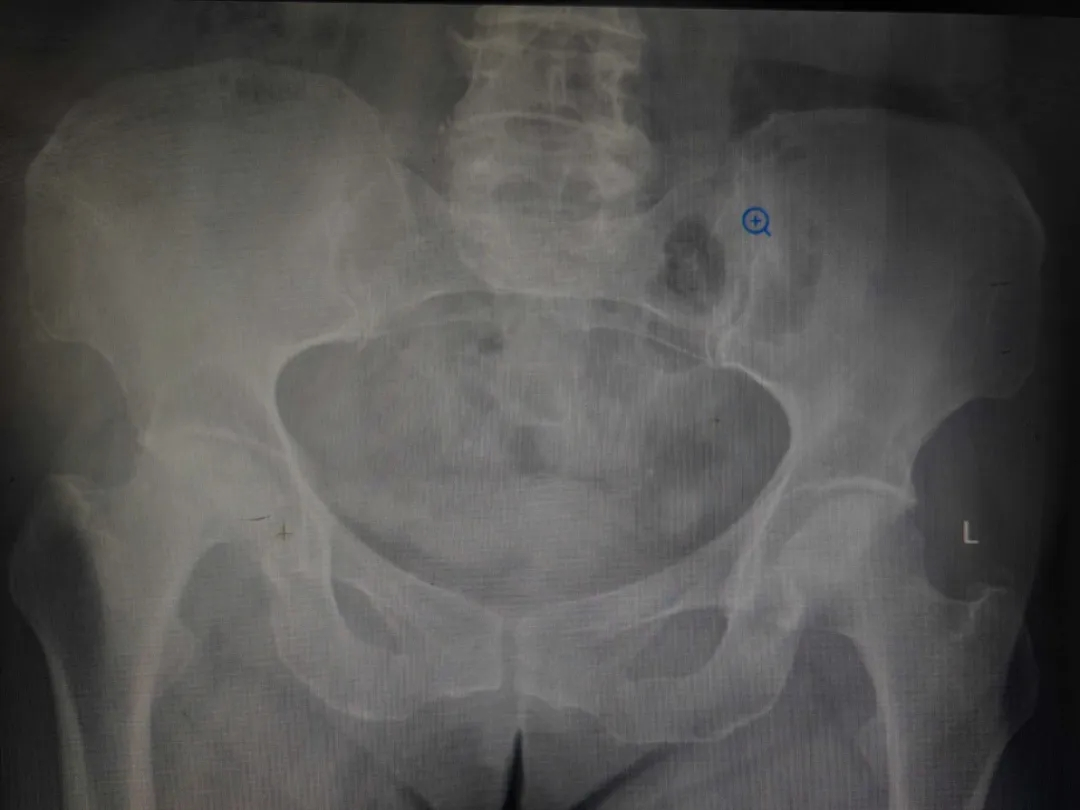

近年来,她的右侧髋关节疼痛日益加剧,从行走困难发展到夜间静息痛,甚至连简单的翻身都成了折磨。影像检查结果显示,她的右侧股骨头已严重塌陷、变形,关节间隙几乎消失。

骨伤科创伤关节团队则利用先进的计算机三维重建技术,在术前精准还原了严重变形股骨头的复杂形态,为假体型号选择、安放角度和骨缺损修复做好了数字化预演。